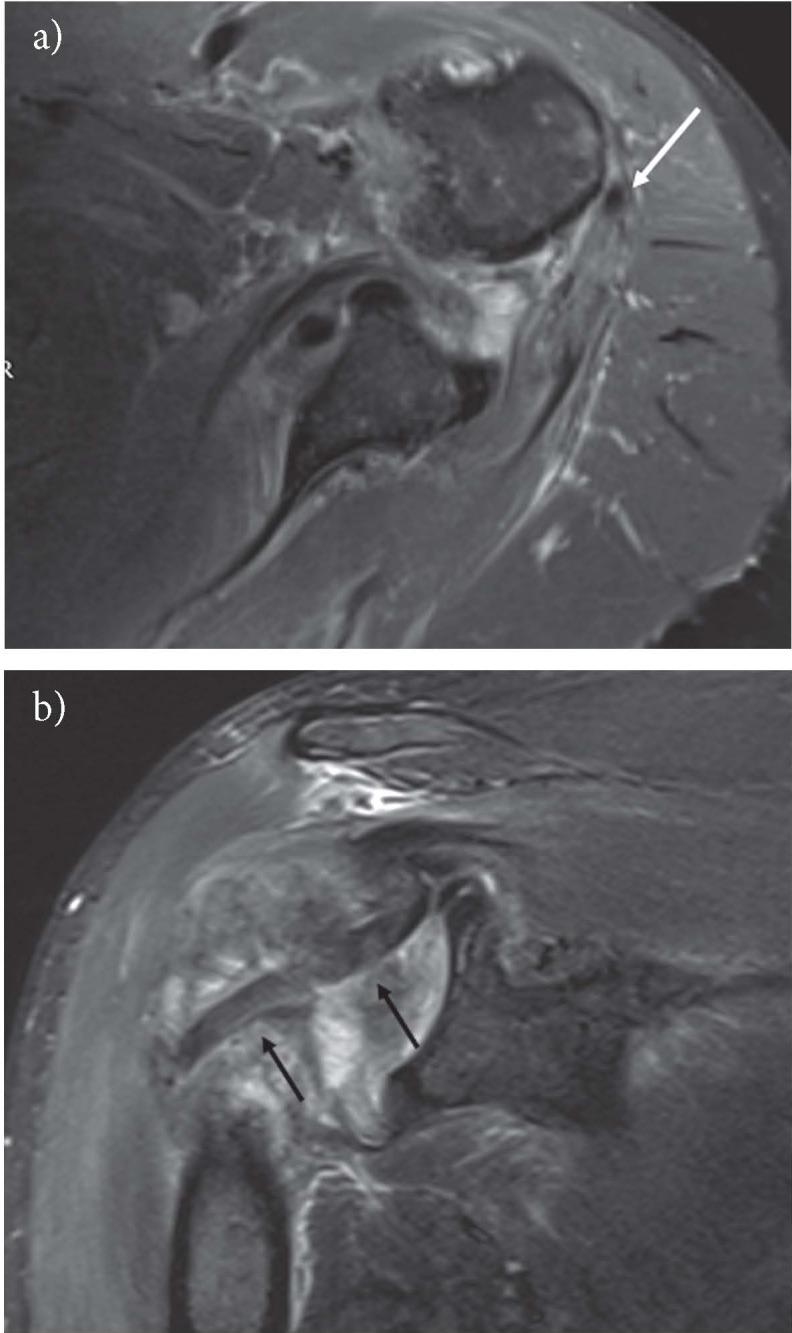

The aim of this is article is to provide an  imaging review of normal anatomy, most common anatomical variants and pathologies of the long head of the biceps tendon (LHB) encountered during the daily practice.

本文的目的是对日常实践中遇到的肱二头肌长头肌腱(LHB)的正常解剖结构、最常见的解剖变异和病变进行影像学综述。